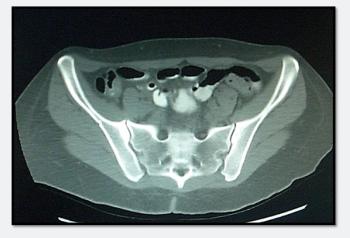

Does the abdominal CT shown offer a clue to the cause of this repeat but markedly more severe episode of hematochezia?